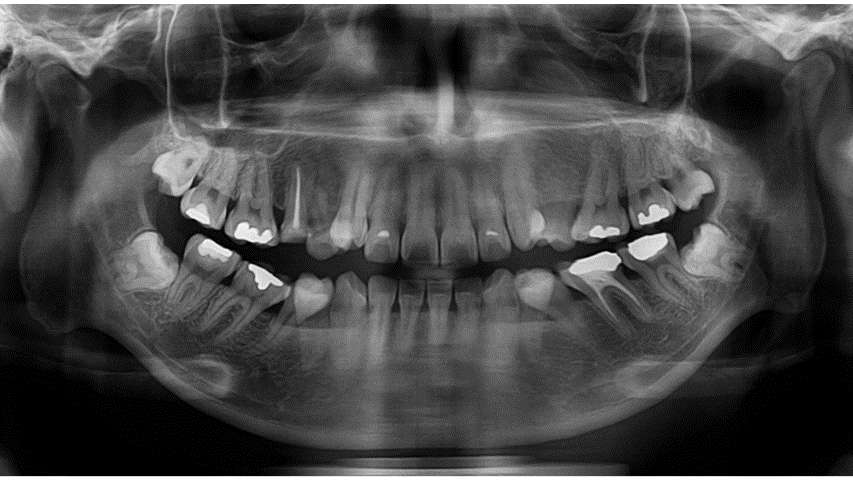

2025.11.15골격성 2급 부정교합, 파절된 치아, 치아 결손으로 인한 대구치 전방이동, 설측경사된 하악 소구치와 이로 인한 대구치의 전방경사, 높은 견치 등 복합적인 문제를 가진 환자를

미니스크류 후방이동·브라켓 부착 준비·치간삭제를 통해 안정적 교합으로 완성한 판교교정치과의 실제 증례입니다.

이번 환자분은 처음 내원하셨을 때부터 여러 치아 문제들이 동시에 존재하는 케이스였습니다.

단순 배열 문제가 아니라, 치아 결손·치아 경사·대구치 전방이동· 송곳니 덧니·치아 파절·충치 다수·심미적 문제가 한꺼번에 얽혀 있었죠.

• 골격성 2급 부정교합

• 상악 우측 제2소구치 : 신경치료 후 크라운 수복을 미루다가 치아 파절

• 상악 좌측 제2소구치 결손 → 좌측 상악 대구치들의 전방이동

• 상악 양측 견치 공간 부족 → 높은 위치(High Canine)

• 하악 제2소구치 양측 모두 심한 설측경사

→ 그 공간으로 제1대구치가 전방 쓰러져 제2소구치의 공간이 거의 없는 상태

• 구강 내 충치 및 수복 필요 치아 다수

• 상악 전치부 순면 변연융선이 과도하게 발달 → 심미적 문제 + 브라켓 부착 어려움